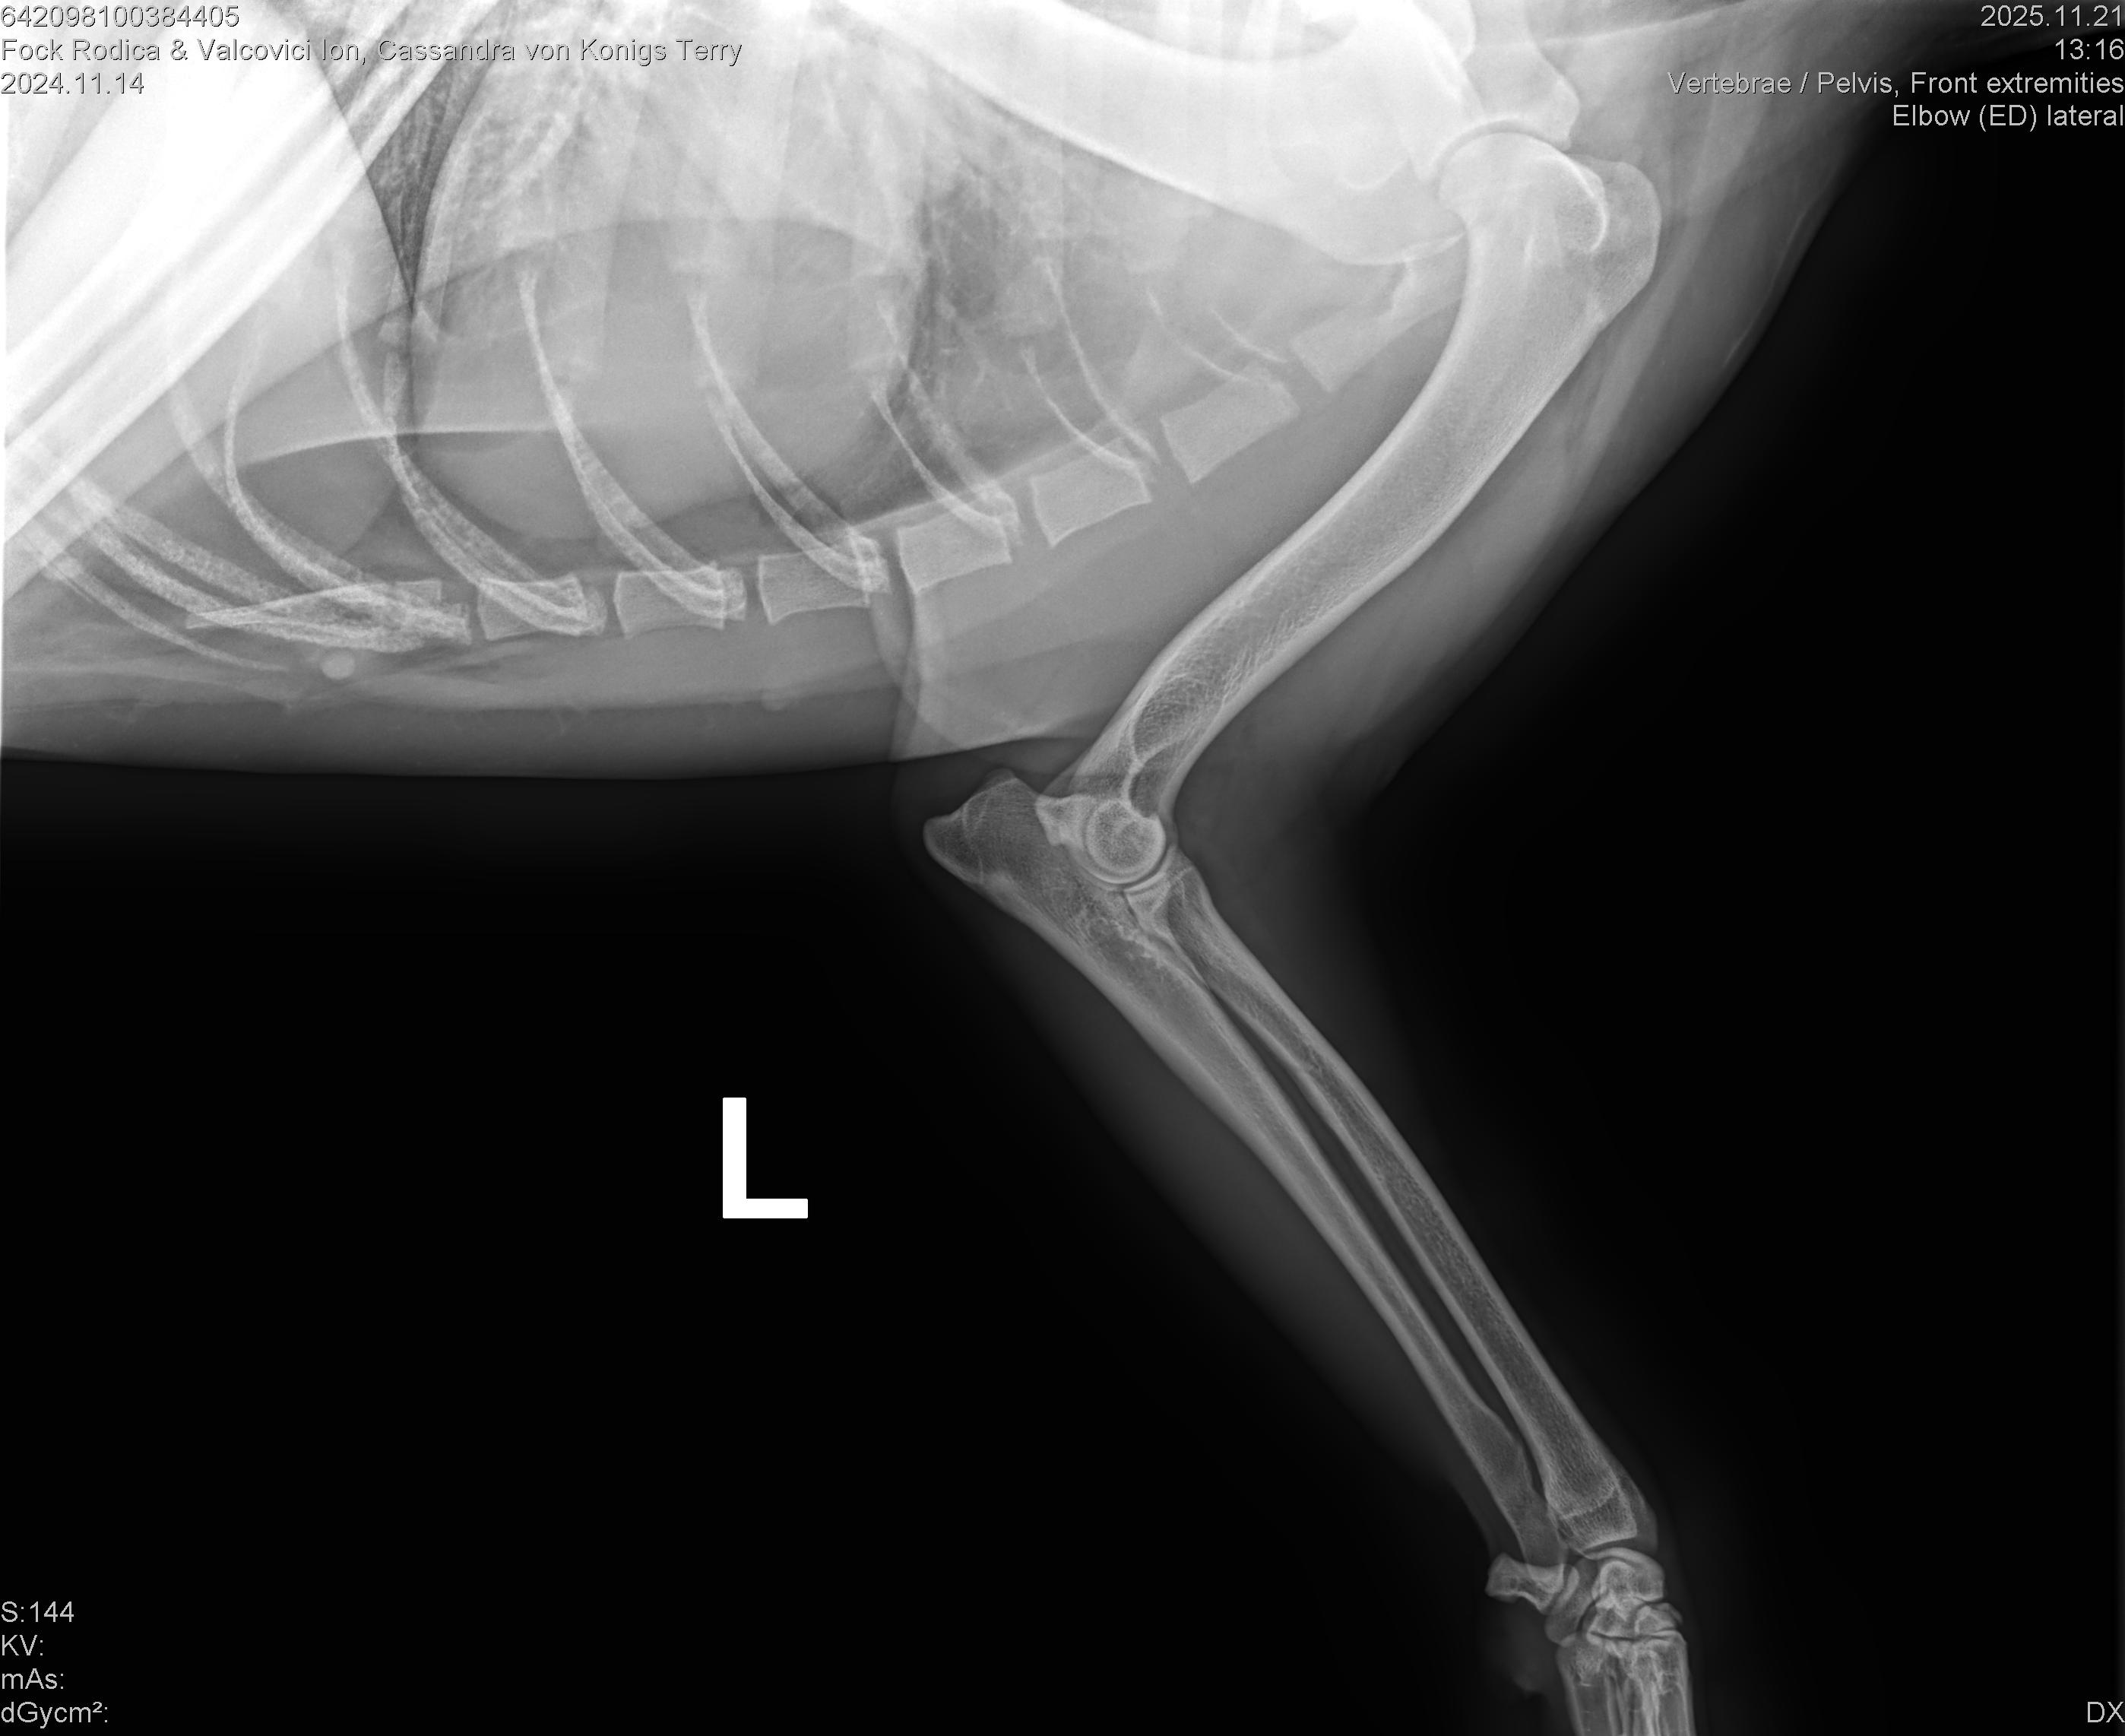

CASSANDRA VON KONIGS-TERRY

( CASSY )

Data nasterii:

14.11.2024

Crescator:

FOCK RODICA si VALCOVICI ION